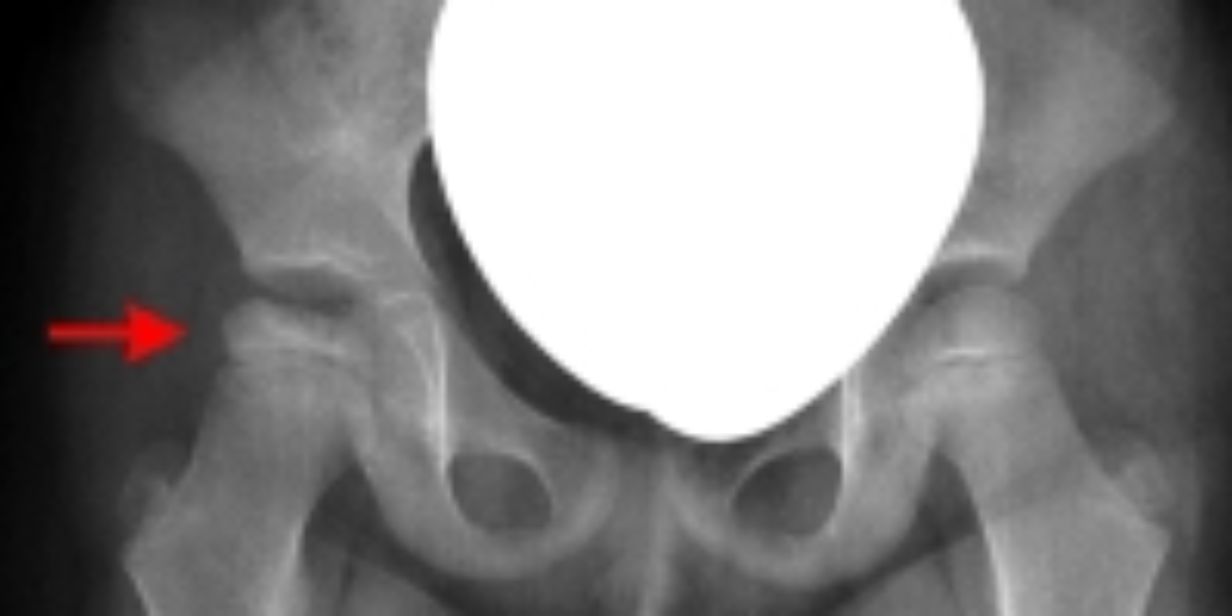

Morbus Perthes

Morbus Perthes bezeichnet eine Durchblutungsstörung des Hüftkopfes während der Wachstumsphase.Die Behandlung richtet sich nach dem Schweregrad der Osteochondrose und der Belastung in der betroffenen Region. Perthes’ DiseaseDer Morbus Perthes stellt die häufigste aseptische Knochennekrose des Kindesalters dar.Die Erkrankung verläuft uneinheitlich, sodass die Therapie individuell erfolgen muss.Konservative Therapie bei Knorpelschäden im oberen Sprunggelenk. Der Einsatz und die Auswahl einer passenden Therapie basiert auf . Die Therapie bei einer Osteochondrose richtet sich nach verschiedenen Kriterien, etwa dem Schweregrad der Erkrankung, den Symptomen und dem allgemeinen Gesundheitszustand von Betroffenen. Von zentraler Bedeutung ist die Verhinderung von .Der Morbus Perthes ist eine idiopathische, aseptische Knochennekrose des kindlichen Hüftkopfes.

Morbus Perthes – eine aseptische Osteochondrose Morbus Perthes ist eine aseptische (keimfreie) Osteochondrose des kindlichen Hüftkopfs und zählt zu den häufigsten orthopädischen Erkrankungen des Hüftgelenks bei Kindern im entsprechenden Alter. Ist das akute Stadium abgeklungen, kommt es darauf an, die Gelenkigkeit innerhalb der Wirbelsäule zu verbessern. Die Behandlung stellt hohe Anforderungen an den orthopädischen Facharzt und wird .Osteochondrose in der LWS behandeln:Die Verschleißerkrankung lässt sich mit den richtigen Übungen, Ernährung und weiteren ganzheitlichen Ansätzen aufhalten.Du leidest unter starken Schmerzen im Rücken? Wir sind auf Osteochondrose Behandlung spezialisiert! Mache noch heute einen Termin aus! Eine Behandlung wird nur deshalb durchgeführt, da hier das Risiko einer Verformung des Hüftkopfes . Welche Symptome treten bei einer Hüftkopfnekrose auf? Diagnose der Hüftkopfnekrose.Behandlung des Morbus Perthes – Morbus Perthesmorbus-perthes.Aseptische Knochennekrose ist ein Sammelbegriff für Nekrosen von Knochen (Osteonekrosen), die nicht durch eine Infektion, sondern aseptisch, zum.Wie kommt es durch eine Schwangerschaft zur Osteochondrose?Die Schwangerschaft selbst verursacht keine Osteochondrose.Moosana Blog: Diagnose Calvé-Legg-Perthes beim Hund. Die Degeneration von Band.Sie reicht von Maßnahmen wie Entlasten des Hüftgelenks mit Gehstöcken und Rollstuhl sowie Krankengymnastik bis hin zur (selten erforderlichen) Operation.

Die Krankheitsdauer beträgt zwischen sechs Monaten und fünf Jahren. De twee bekendste vormen van osteochondrose zijn .Wann sollte man mit einer Osteochondrose zum Arzt?Verspüren Sie lokal in einem Gelenk mittelstarke Schmerzen ohne Ausstrahlung in andere Bereiche des Körpers, empfehle ich Ihnen den Besuch bei eine.Welche Erfahrungen haben die Spezialisten der Gelenk-Klinik mit Osteochondrose?Die Orthopäden und Rückenexperten der Gelenk-Klinik sind auf die Behandlung der Osteochondrose in allen Formen und Schweregraden spezialisiert. Bei der Osteochondrose-Behandlung gehen wir ganz auf Ihre Bedürfnisse ein.Hüftkopfnekrose beim Kind: Morbus Perthes. Welche Therapie kann das Absterben der .Hüftkopfnekrose beim Kind: Morbus Perthes; Welche Symptome treten bei einer Hüftkopfnekrose auf? Diagnose der Hüftkopfnekrose; Welche Therapie kann das Absterben der Knochenzellen bei einer Hüftkopfnekrose stoppen? Durch eine Minderdurchblutung wird der Hüftkopf nicht mehr ausreichend mit Nährstoffen versorgt.Morbus Perthes ist eine aseptische (keimfreie) Osteochondrose des kindlichen Hüftkopfs und zählt zu den häufigsten orthopädischen Erkrankungen des Hüftgelenks bei Kindern .Wat is osteochondrose? Osteochondrose is een degeneratieve aandoening van de botten. (Siehe auch Übersicht zu Knochenerkrankungen bei Kindern. Bei typischem Verlauf wird die Femurkopfepiphyse erst abgebaut und infolge von ReparationsprozDie Osteochondrose im Hüftgelenk wird medizinisch als Osteochondrosis dissecans coxae bezeichnet.